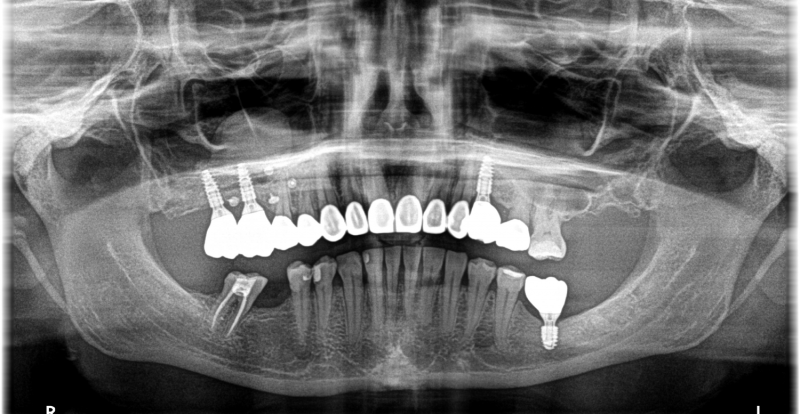

Wykonana praca protetyczna:

- licówki pełnoceramiczne w odcinku przednim zębów górnych

- korony pełnoceramiczne na zęby własne zarówno w łuku dolnym i górnym

- korony na implantach braków zębów